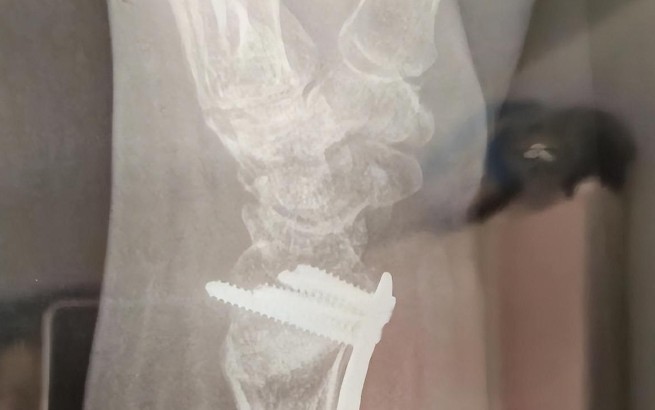

Rêvez d’une opération du poignet

Rêver de subir une opération du poignet est un signe que vous devez fondamentalement changer pour résoudre un problème sérieux que vous rencontrez. La chirurgie est une étape nécessaire à la guérison et à la récupération, et la chirurgie du poignet peut signifier une décision importante pour restaurer vos capacités ou votre fonction. Rêver d’un poignet cassé est le signe que vous devez prendre une décision importante pour surmonter vos difficultés actuelles. Cela peut aussi symboliser le processus d’acceptation des changements nécessaires dans votre vie et de préparation à de nouveaux départs.

Rêve de subir une opération pour traiter une blessure au poignet

La chirurgie pour traiter une blessure au poignet symbolise le processus nécessaire pour résoudre un grand problème dans la vie. La chirurgie peut être un processus douloureux et effrayant, mais elle constitue une étape importante pour finalement restaurer la capacité ou la fonction. Rêver d’un poignet cassé peut être un signe que vous devez accepter les changements nécessaires pour faire face aux problèmes que vous traversez actuellement et vous préparer à un nouveau départ. Cela peut aussi indiquer que vous devez prendre des décisions importantes pour surmonter les défis à présenter.